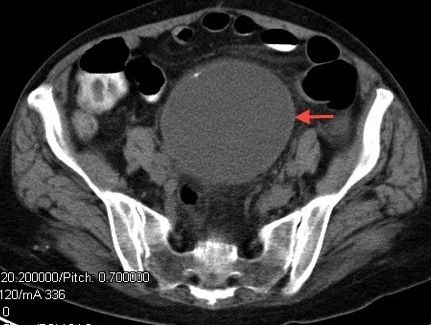

An abdominal series showed no free air and no fluid levels in the bowel. Contrast-enhanced CT scan of the abdomen and pelvis revealed no evidence of colonic inflammation or bowel abnormalities. However, there was a 9.4 x 8.7 x 10-cm cystic structure with punctate calcifications in the retroperitoneum arising from the outer curvature of the 3rd portion of the duodenum and extending to the aortic bifurcation (Figure 1). A diagnosis was made of a large retroperitoneal cyst and exploratory laparotomy was scheduled for the following day.